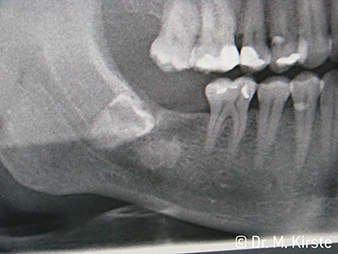

W&H X-Ray

Fig. 6: Patient example: The displaced tooth 48 ...